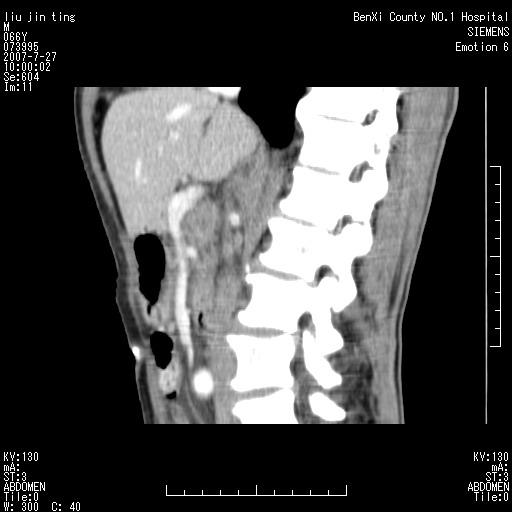

腹痛,背痛,无恶心呕吐,不黄,彩超示胰腺钩癌,ct扫描病灶平扫30-40hu,增强后动脉期40--60hu,静脉期50-68hu,真的是钩突上的么?您要试一试么?

动脉期

静脉期